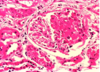

what is shown here?

Glomerulus with membranous disease causing a thickened glomerular basement membrane